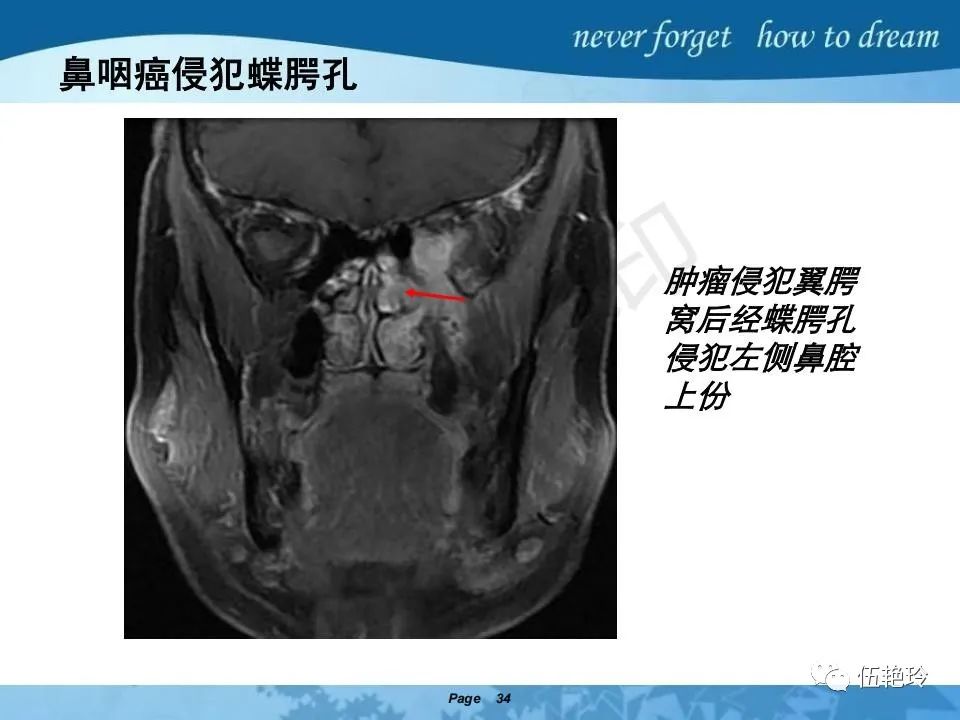

翼腭窝的解剖结构与鼻咽癌侵犯

2.31 向上颅内:①鼻咽顶壁→破裂孔(岩尖、斜坡)→蝶窦、海绵窦;②鼻咽顶壁→蝶骨基底部→蝶窦、海绵窦;③鼻咽侧壁→茎突前间隙→蝶骨大翼(卵圆孔)→海绵窦;④鼻咽侧壁→茎突前间隙→翼腭窝→ 颞下窝;⑤鼻咽前壁→鼻腔→翼突、翼腭窝→眶下裂→眶尖→海绵窦;⑥鼻咽前壁→鼻腔→上颌窦、筛窦;